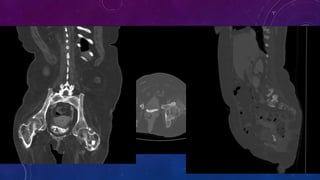

• Multiple pelvic phleboliths.

• Small well-defined round osseous lesions in the left

side of the abdomen, adjacent to midline represent

calcified lymph node in the para-aortic and left

common iliac groups, also visualized on the

corresponding CT.